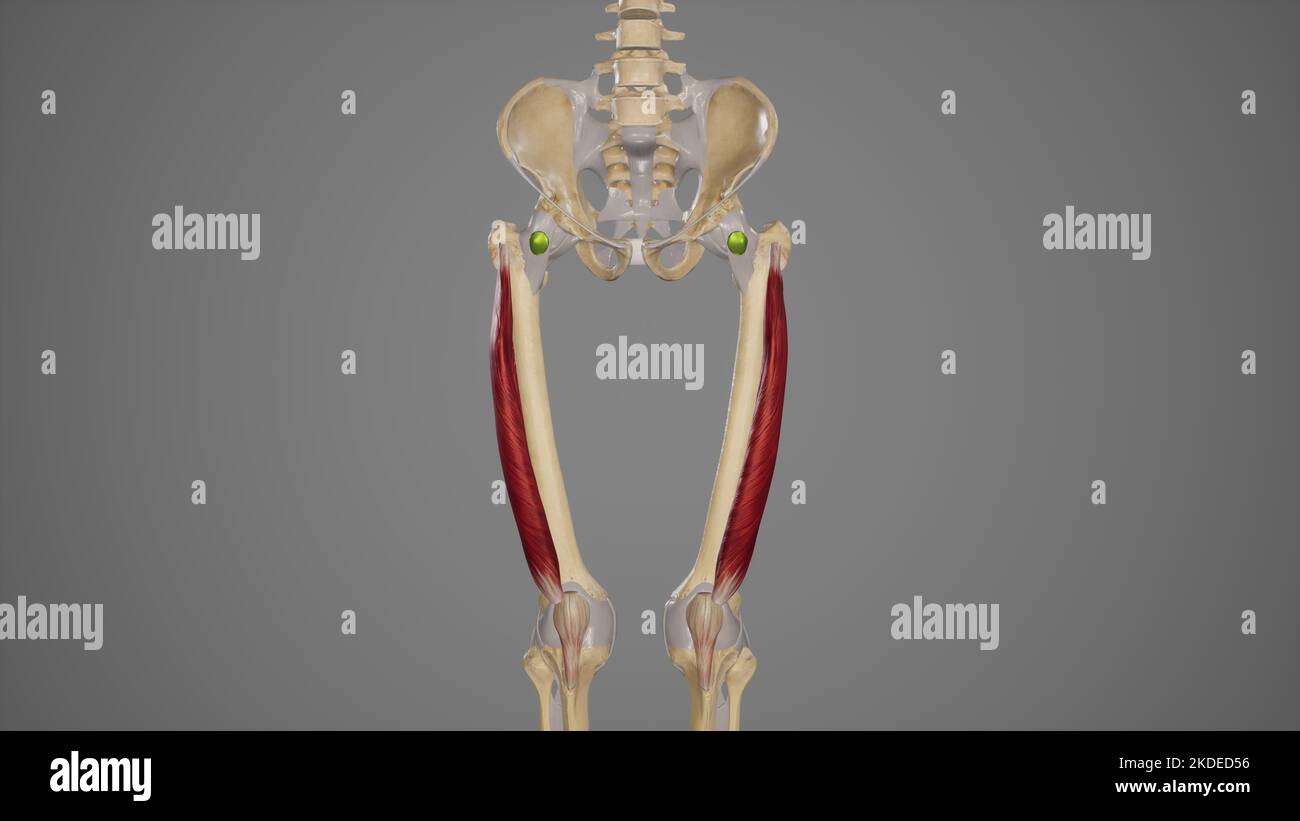

Muscle quadriceps surligné avec membre inférieur Banque D'Imageshttps://www.alamyimages.fr/image-license-details/?v=1https://www.alamyimages.fr/muscle-quadriceps-surligne-avec-membre-inferieur-image629479639.html

Muscle quadriceps surligné avec membre inférieur Banque D'Imageshttps://www.alamyimages.fr/image-license-details/?v=1https://www.alamyimages.fr/muscle-quadriceps-surligne-avec-membre-inferieur-image629479639.htmlRF2YG37KK–Muscle quadriceps surligné avec membre inférieur

Illustration médicale du muscle vastus lateralis Banque D'Imageshttps://www.alamyimages.fr/image-license-details/?v=1https://www.alamyimages.fr/illustration-medicale-du-muscle-vastus-lateralis-image490198498.html

Illustration médicale du muscle vastus lateralis Banque D'Imageshttps://www.alamyimages.fr/image-license-details/?v=1https://www.alamyimages.fr/illustration-medicale-du-muscle-vastus-lateralis-image490198498.htmlRF2KDED56–Illustration médicale du muscle vastus lateralis